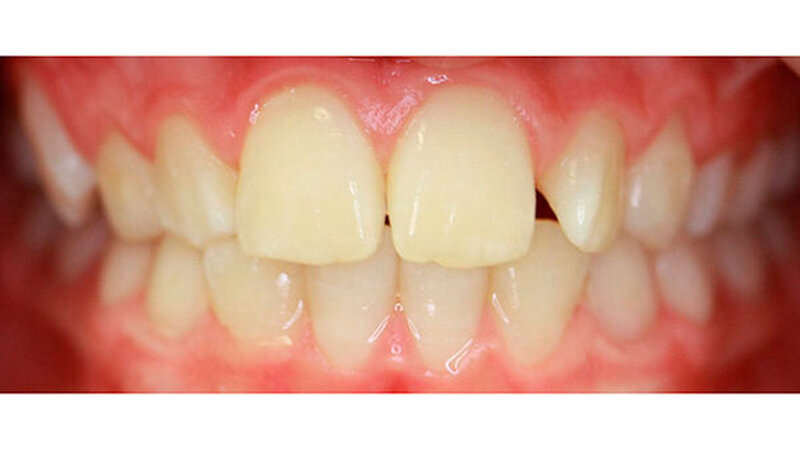

Dieser Fallbericht zeigt eine Patientin mit einer Transposition und multiplen verlagerten Zähnen, die mithilfe eines Gaumenimplantats eingeordnet wurden. Das Mädchen stellte sich im Alter von 13,7 Jahren in unserer Praxis vor. Bei der klinischen Untersuchung fiel die Persistenz mehrerer Milchzähne auf. Der Zahn 13 war distal des Milchzahns 53 durchgebrochen.

Im Rahmen der Modellanalyse ergaben sich folgende Befunde: Im Oberkiefer lagen außer der Transposition der Zähne 13 und 14 multiple Rotationen und Kippstände vor. Die Unterkieferfront wies einen Engstand auf. Im Molarenbereich lag beidseits eine Distalokklusion von ¼ Prämolarenbreite vor. Der Overjet betrug 2 mm, der Overbite 3 mm. Die Zähne 22/33, sowie 24/74 wiesen eine Kopfbissrelation auf.